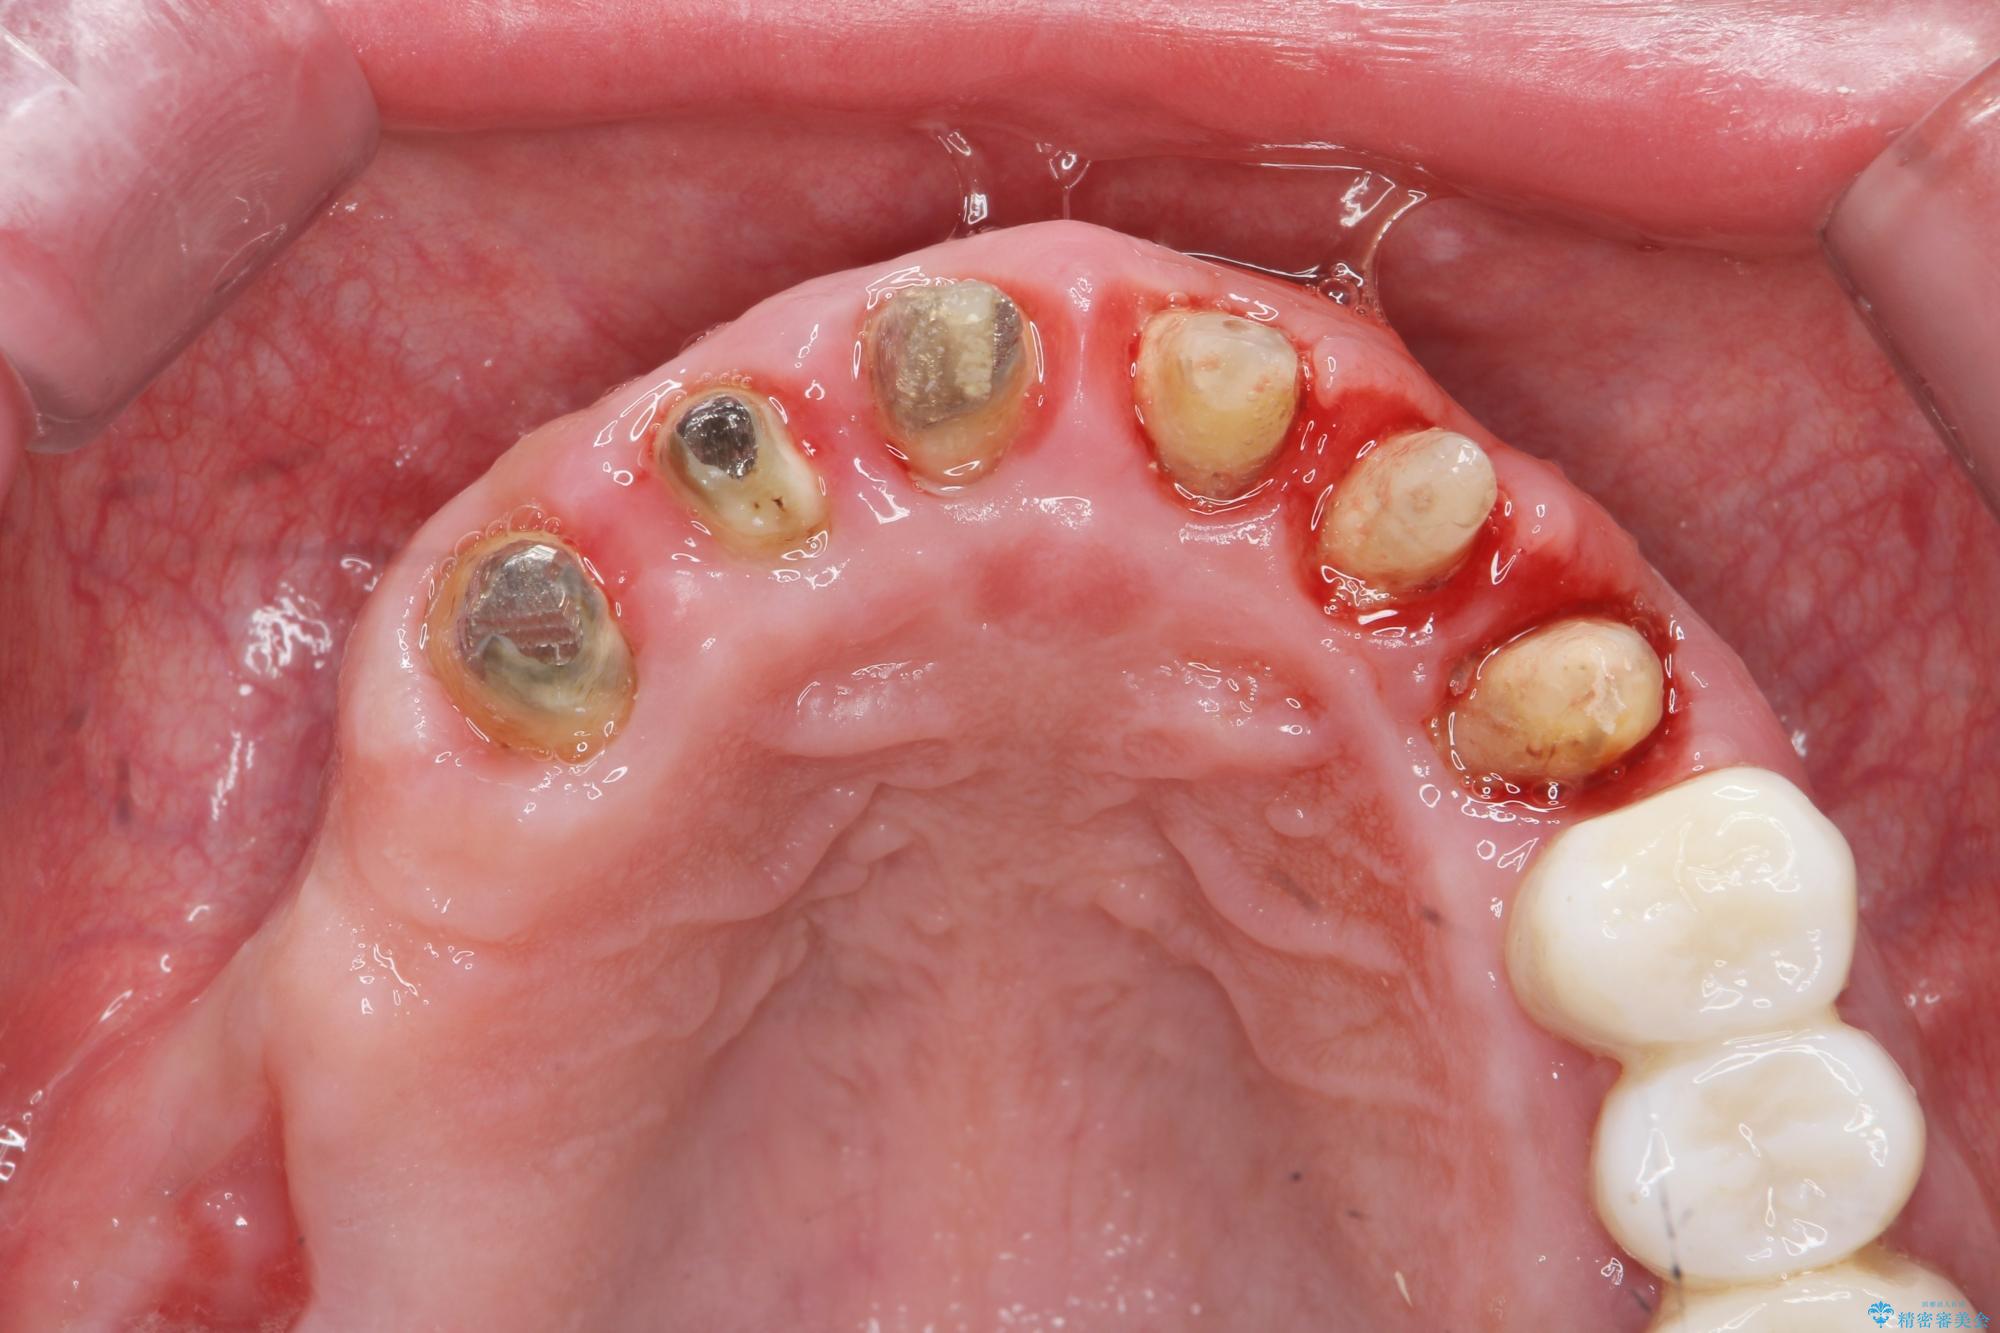

- 「セラミック治療を他院で受けたが、それ以来歯ぐきが腫れ違和感がある、改善してほしい。」と歯ぐきの状態改善を希望され来院されました。

歯周組織検査を行うと歯ぐきからは容易に出血し、X線検査より歯とセラミッククラウンの適合が悪い(ピッタリと合っていない)状態が示唆され、歯ぐきの炎症を惹起している状態でした。

セラミッククラウンを除去し仮歯を装着し、歯周外科手術を行い歯ぐきの状態を改善したのち、適合の良いセラミッククラウンを再作製をする治療計画としました。

- 90.2万円(ジルコニアクラウン×6・仮歯×6 ・歯周外科手術)費用は治療当時の料金となります